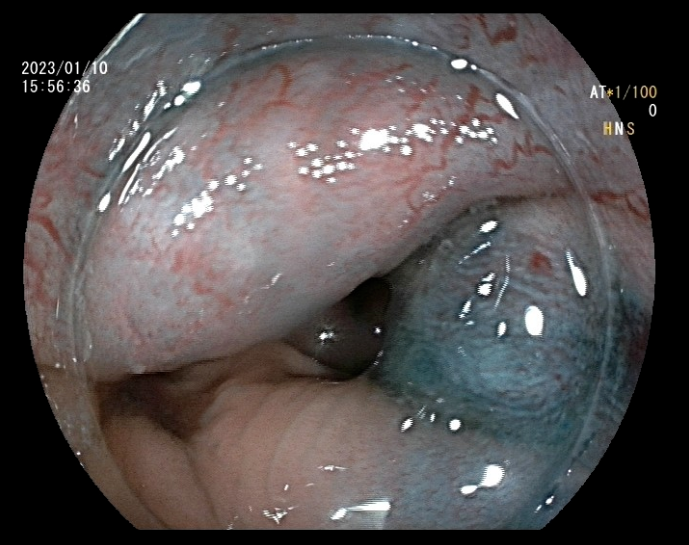

近日,北京燕化医院消化内科再次完成一例内镜下内痔硬化剂注射术,成功为患者解决长期便血的困扰。

患者李某,男,48岁,主因间断便血2月余,加重20天入院。既往高血压病1级(低危)、高脂血症。患者饱受2个多月间断鲜血便的困扰,且便后伴有异物脱出,门诊以“II期内痔伴出血”收入消化内科。消化内科副主任王铁汉查房时,根据患者目前状况及手术耐受情况,建议其行内镜下内痔硬化剂注射术,并与患者讲解了此术式的优点及相关事项,经过衡量再三,患者同意实施内镜下治疗。

入院的第三天,张芙蓉主治医师在王铁汉副主任的指导下,为患者实施内镜下内痔硬化剂注射术,仅数分钟,手术成功完成。术后患者无任何不适症状,并于三日后出院,术后第7、15天随访,患者表述术后未感觉到任何不适,困扰多月的血便问题得以完美解决。

近几年,内镜下内痔硬化剂治疗术已广泛应用于各大医院,该治疗方法适用于I期、II期、III期内痔及混合痔内痔部分,尤其是内痔出血患者效果尤佳。患者接受程度高、效果满意。该治疗在做电子结肠镜过程中即可完成,较传统的痔疮治疗方法,操作简单,患者痛苦小,疗效好,并发症少,且花费低,患者耐受性好,术后观察2-3天无不适症状即可出院。